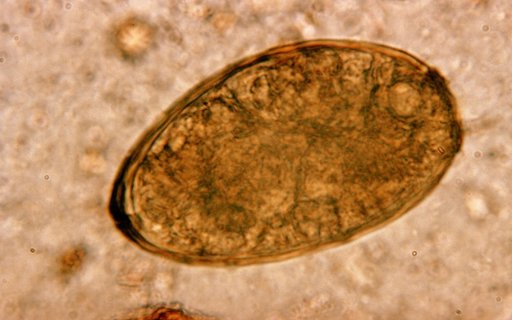

Bệnh sán lá phổi do 40 loài khác nhau gây ra thuộc giống Paragonimiasis được phát hiện ở rất nhiều nơi, tại Việt Nam do loài sán Paragonimus heterotremus ký sinh trong phổi hoặc màng phổi gây ra. Tùy từng giai đoạn của bệnh mà có triệu chứng như đau bụng tiêu chảy cho đến tổn thương phổi thậm chí...